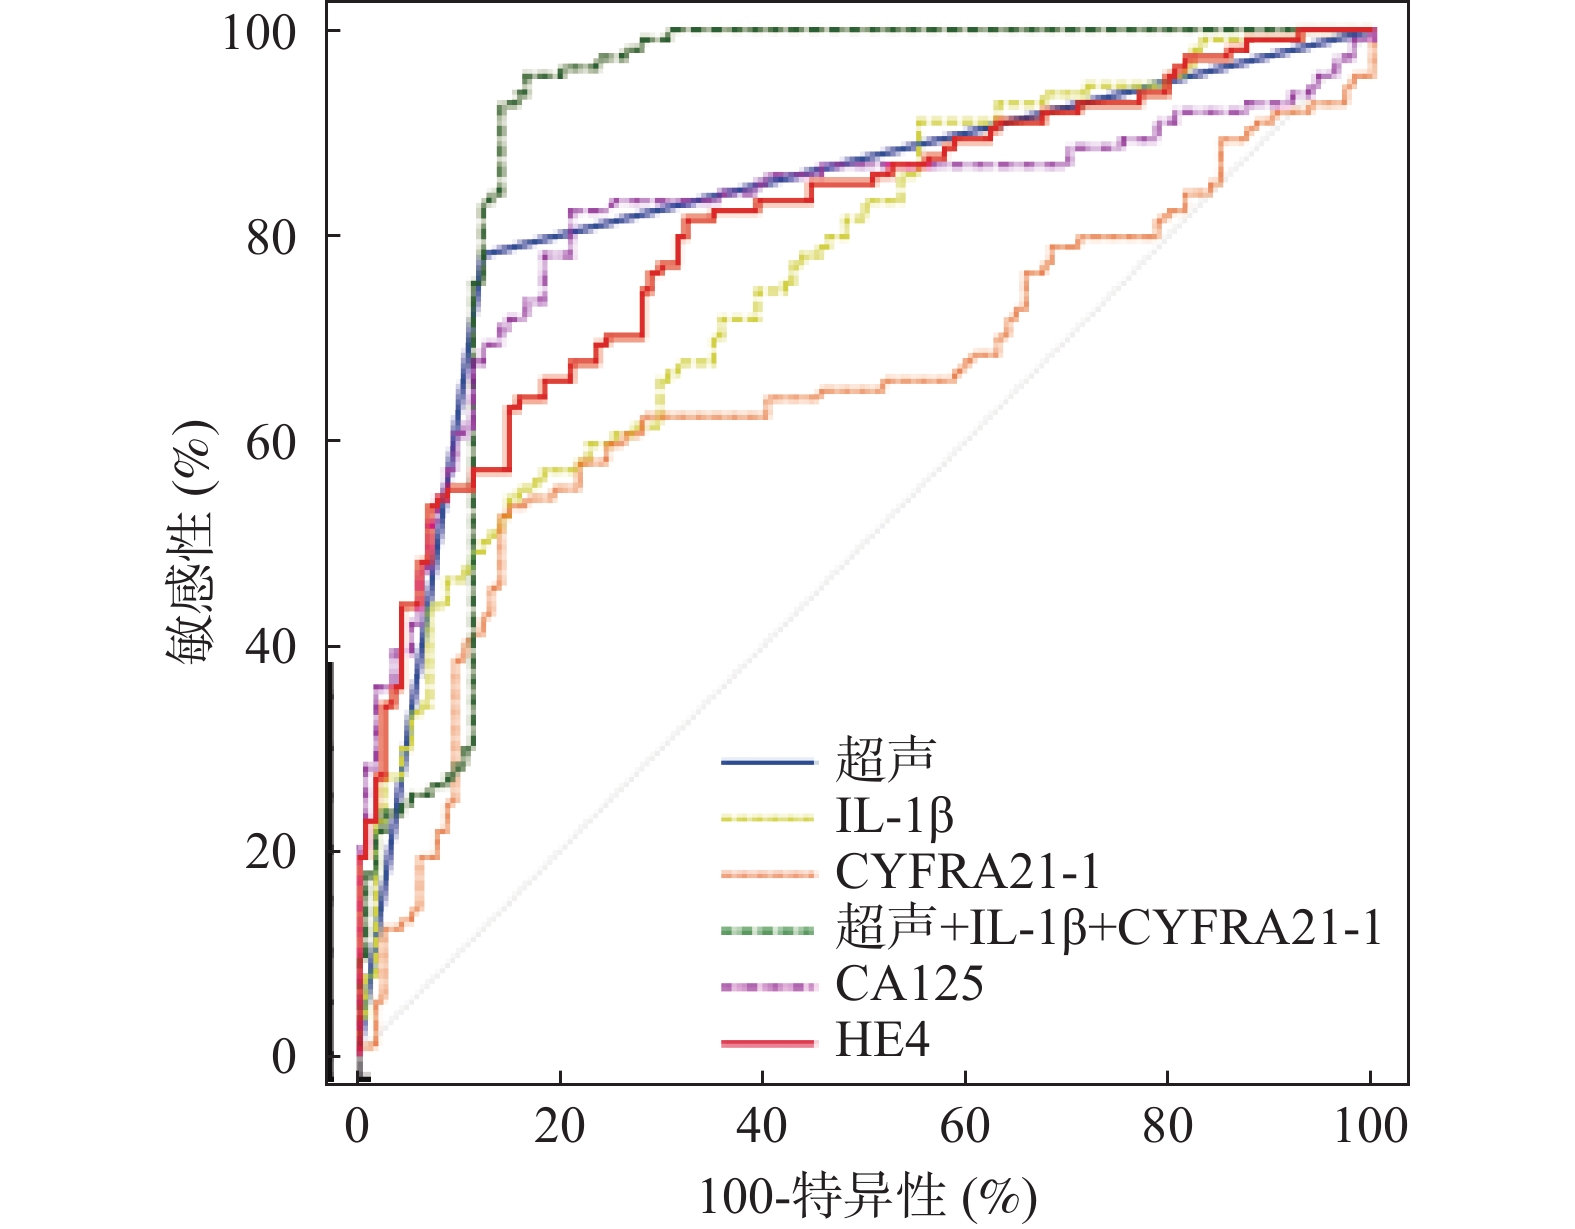

目的 探究超声联合血清白细胞介素-1β(interleukin-1β,IL-1β)、C角蛋白19片段抗原21-1(cytokeratin 19 fragment antigen 21-1,CYFRA21-1)对卵巢癌的诊断价值。 方法 于2020年7月至2023年7月选取沧州中西医结合医院收治的卵巢肿瘤患者250例,经病理检测确诊为卵巢癌的患者114例即为卵巢癌组,从136例良性肿瘤患者中随机选择114例卵巢良性病变患者即为对照组。采用彩色超声诊断仪对所有研究对象进行诊断。采用酶联免疫吸附(enzyme linked immunosorbent assay,ELISA)法检测血清中IL-1β、CYFRA21-1水平。Kappa检验分析诊断方法与手术病理结果的一致性。多因素Logistic回归分析卵巢癌发生影响因素。受试者工作特征(receiver operating characteristic,ROC)曲线分析超声联合血清IL-1β、CYFRA21-1对卵巢癌的诊断价值。 结果 卵巢癌组患者血清中IL-1β、CYFRA21-1水平与对照组相比显著升高(P < 0.05)。与透明细胞癌相比,粘液性腺癌和浆液性腺癌患者血清中IL-1β、CYFRA21-1水平依次显著升高(P < 0.05)。卵巢癌患者血清中IL-1β、CYFRA21-1水平在Ⅰ期<Ⅱ期<Ⅲ期<Ⅳ期(P < 0.05)。血清IL-1β、CYFRA21-1水平升高是卵巢癌发生的危险因素(P < 0.05)。超声联合血清IL-1β、CYFRA21-1对卵巢癌诊断的曲线下面积(area under the curve,AUC)显著高于单一指标诊断的AUC值(Z超声~超声+IL-1β+CYFRA21-1=3.782,P < 0.001;ZIL-1β~超声+IL-1β+CYFRA21-1=4.046,P < 0.001;ZCYFRA21-1~超声+IL-1β+CYFRA21-1=7.279,P < 0.001)。以病理检查结果为依据,联合诊断的一致性(Kappa值=0.789)高于超声(Kappa值=0.658)单独诊断。 结论 超声联合血清IL-1β、CYFRA21-1对卵巢癌的诊断效能较高。 -

Abstract:Objective To explore the diagnostic value of ultrasound combined with serum interleukin-1β (IL-1β) and cytokeratin 19 fragment antigen 21-1 (CYFRA21-1) in ovarian cancer. Methods From July 2020 to July 2023, 250 patients with ovarian tumors admitted to Cangzhou Integrated Chinese and Western Medicine Hospital were enrolled. Among them, 114 patients confirmed as having ovarian cancer by pathological examination comprised the ovarian cancer group. Additionally, 114 patients were randomly selected from the remaining 136 patients with benign tumors to form the control group. All study subjects underwent diagnosis using color ultrasound diagnostic equipment. Serum levels of IL-1β and CYFRA21-1 were detected using the enzyme linked immunosorbent assay (ELISA) method. Kappa test was used to analyze the consistency between diagnostic methods and surgical pathological results. Multivariate logistic regression analysis was performed to identify risk factors for ovarian cancer occurrence. Receiver operating characteristic (ROC) curve analysis was used to evaluate the diagnostic value of ultrasound combined with serum IL-1β and CYFRA21-1 for ovarian cancer. Results Serum levels of IL-1β and CYFRA21-1 in the ovarian cancer group were significantly elevated compared to the control group (P < 0.05). Compared with clear cell carcinoma, serum levels of IL-1β and CYFRA21-1 in patients with mucinous adenocarcinoma and serous adenocarcinoma were significantly elevated (P < 0.05). Serum levels of IL-1β and CYFRA21-1 in ovarian cancer patients showed a progressive increase across stages I<stage II<stage III<stage IV (P < 0.05). Elevated serum levels of IL-1 β and CYFRA21-1 were risk factors for ovarian cancer (P < 0.05). The area under the curve (AUC) for the combined ultrasound with serum IL-1β and CYFRA21-1 in diagnosing ovarian cancer was significantly higher than the AUC values of single-indicator diagnosis (Zultrasound~ultrasound+IL-1β+CYFRA21-1=3.782, P < 0.001; ZIL-1β~ultrasound+IL-1β+CYFRA21-1=4.046, P < 0.001; ZCYFRA21-1~ultrasound+IL-1β+CYFRA21-1=7.279, P < 0.001). Based on pathological examination results, the consistency of combined diagnosis (Kappa value=0.789) was higher than ultrasound alone (Kappa value=0.658). Conclusion The combined diagnostic approach of ultrasound with serum IL-1β and CYFRA21-1 demonstrates high diagnostic efficacy for ovarian cancer. -